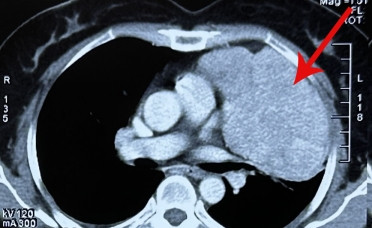

Khi chuyển đến Bệnh viện Ung Bướu Hà Nội, qua các xét nghiệm chụp chiếu, các bác sĩ xác định khối u kích thước 11x10cm đã chèn ép gây xẹp gần như toàn bộ phổi trái, dính vào màng phổi, màng tim và dịch màng phổi tương đối dày.

| Mổ ruột thừa phát hiện u trung thất lớn đẩy xẹp phổi |

TS.BS. Phan Lê Thắng, trưởng khoa Ngoại Theo yêu cầu, bệnh viện Ung bướu Hà Nội cho biết, khối u của bệnh nhân có kích thước lớn, nhiều mạch nuôi, gây tăng sinh mạch máu, dính các tạng xung quanh khiến quá trình phẫu thuật gặp nhiều khó khăn trong việc cầm máu và cắt u.

Kết quả giải phẫu bệnh cho thấy khối u là loại u tuyến ức tuýp AB. U tuyến ức là căn bệnh hiếm gặp hơn so với các bệnh ung thư khác và hầu như không biểu hiện triệu chứng khi ở giai đoạn sớm, tuy nhiên khi mắc căn bệnh này nếu được thăm khám và điều trị kịp thời thì cơ hội sống rất cao.